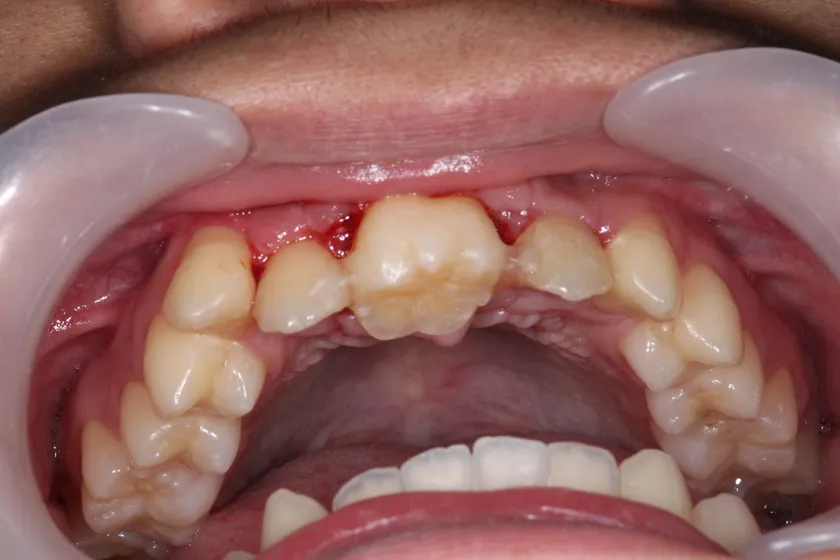

<症例(19歳男性)>

自転車転倒により上の前歯を喪失した患者で入れ歯を入れるも紛失し、インプラント治療以外で治療法がないかと移植に希望をもって当院へ来院されました。当初は下の両側の小臼歯2本を移植し、矯正で抜いた部分を閉鎖しようと検討したものの、矯正医よりスペースの閉鎖は困難と診断され断念。家族、本人の熱意もあり、「埋伏の親知らず」を移植する計画を立て、3D-CTと3Dプリンターを用いての精密なシミュレーションを行った上で施術を行いました。